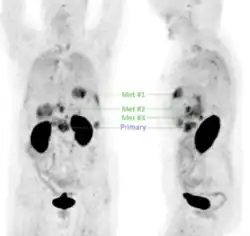

Pancreatic cancer

First-in-human application of different αvβ6-integrin radiotracers has demonstrated that 68Ga-Trivehexin performed especially well in detecting pancreatic cancer, showing high uptake in tumor lesions and low background in the gastrointestinal tract (GI tract) (see image).[30] Since its introduction,[1] 68Ga-Trivehexin has been used predominantly for PET/CT imaging of pancreatic ductal adenocarcinoma (PDAC), for example, in single cases [28][31] and two cohorts (12 and 44 patients, respectively) [32][29] of suspected or known PDAC.